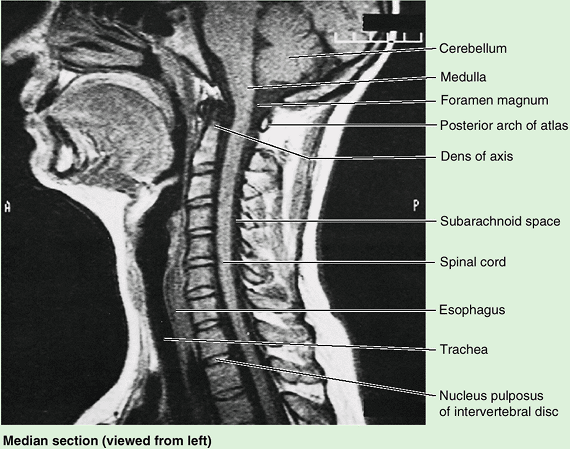

Figure 4.1. Vertebral column and vertebral canal, demonstrating its five regions. A. This anterior view shows the isolated vertebral column. B.

This right lateral view shows the isolated vertebral column. The isolated vertebrae are typical of each of the three mobile regions. Note the increase in size of the vertebrae as the column descends. C. This posterior view of the vertebral column includes the vertebral ends of ribs, representing the skeleton of the back. D. This medial view of the axial skeleton in situ demonstrates its regional curvatures and its relationship to the cranium (skull), thoracic cage, and hip bone. The continuous, weight-bearing column of vertebral bodies and IV discs forms the anterior wall of the vertebral canal. The lateral and posterior walls of the canal are formed by the series of vertebral arches. The IV foramina (seen also in part B) are openings in the lateral wall through which spinal nerves exit the vertebral canal. The posterior wall is formed by overlapping laminae and spinous processes, like shingles on a roof. E. This sagittal MRI study shows the primary contents of the vertebral canal. The medullary cone (L. conus medullaris) is the cone-shaped inferior end of the spinal cord, which typically ends at the L1–L2 level in adults. The dura mater, the external covering of the spinal cord (gray), is separated from the spinal cord by a fluid-filled space (black) and from the wall of the vertebral canal by fat (white) and thin-walled veins (not visible here). |